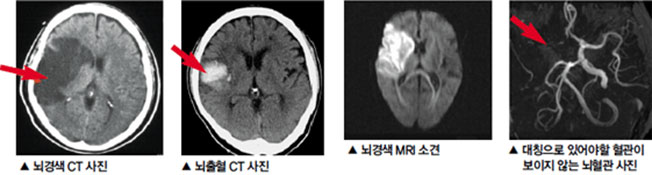

먼저 뇌경색이 무엇인지에 대해 쉽게 설명드리겠습니다. 뇌경색은 뇌로 가는 혈류가 차단되어 발생하는 질병으로, 일반적으로 뇌졸중이라고도 알려져 있습니다. 뇌혈관이 좁아지거나 막히면서 뇌가 필요한 산소와 영양분을 공급받지 못하게 되고, 이로 인해 뇌세포가 손상됩니다. 이러한 손상은 즉각적인 신체 기능 저하를 초래할 수 있으며, 심각한 경우 생명에 지장을 줄 수 있습니다.